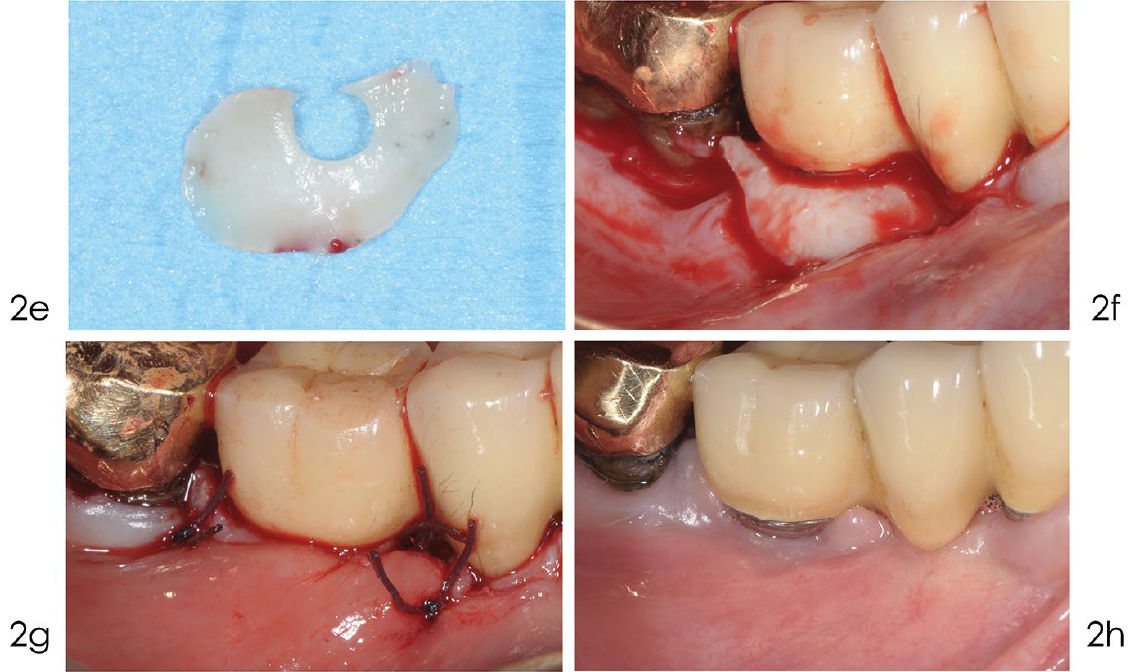

Фото 2e-h. Реконструктивное лечение периимплантита

e) Соединительнотканный трансплантат взят из бугра верхней челюсти и имеет U-образную форму. f) Трансплантат адаптирован вокруг шейки имплантата и полностью закрывает дефект для обеспечения стабильности материала. g) Шов нитью Vicryl 4/0 обеспечивает оптимальное открытое (непогружённое) заживление. h) Оптимальное заживление через год: отсутствуют признаки воспаления, вокруг имплантата сформировалась зона кератинизированной слизистой